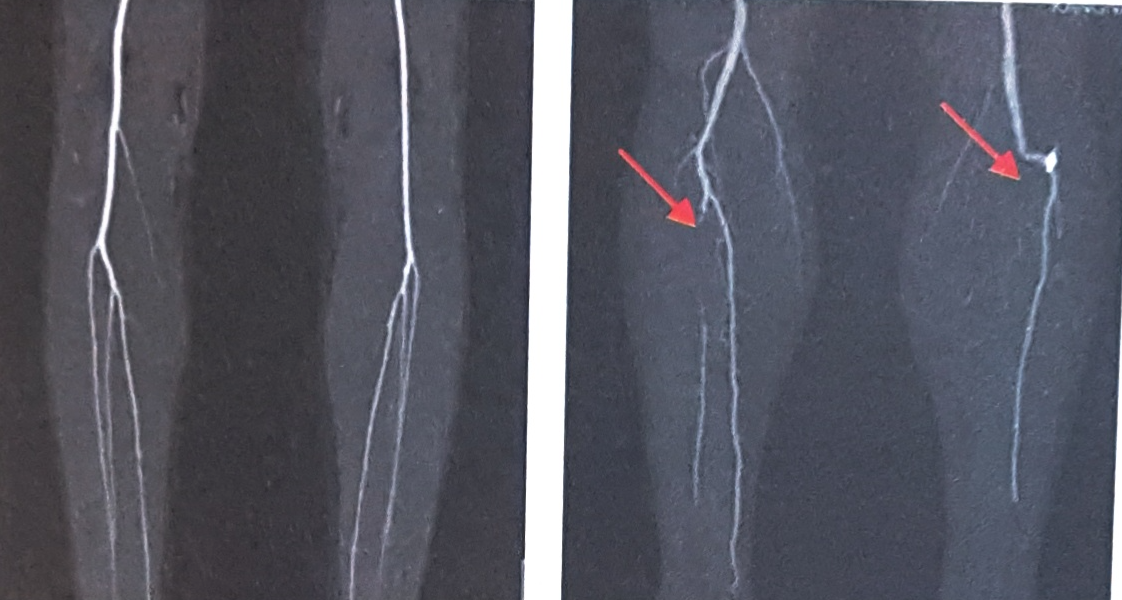

다리의 무릎아래 동맥

CT촬영 종류에는 동맥 및 정맥 혈관 CT, 복부대동맥 CT, 심부정맥혈전 & 폐동맥 CT, 관상동맥 CT 등이 있습니다. 혈관질환의 정확한 검사 및 진단을 위해서는 혈관외과 전문의의 적절한 처방을 받아야 합니다.확인하고자 하는 대상에 따라서 촬영방법이 조금씩 차이가 있으나 기본적으로는 모두 같은 검사방법입니다.